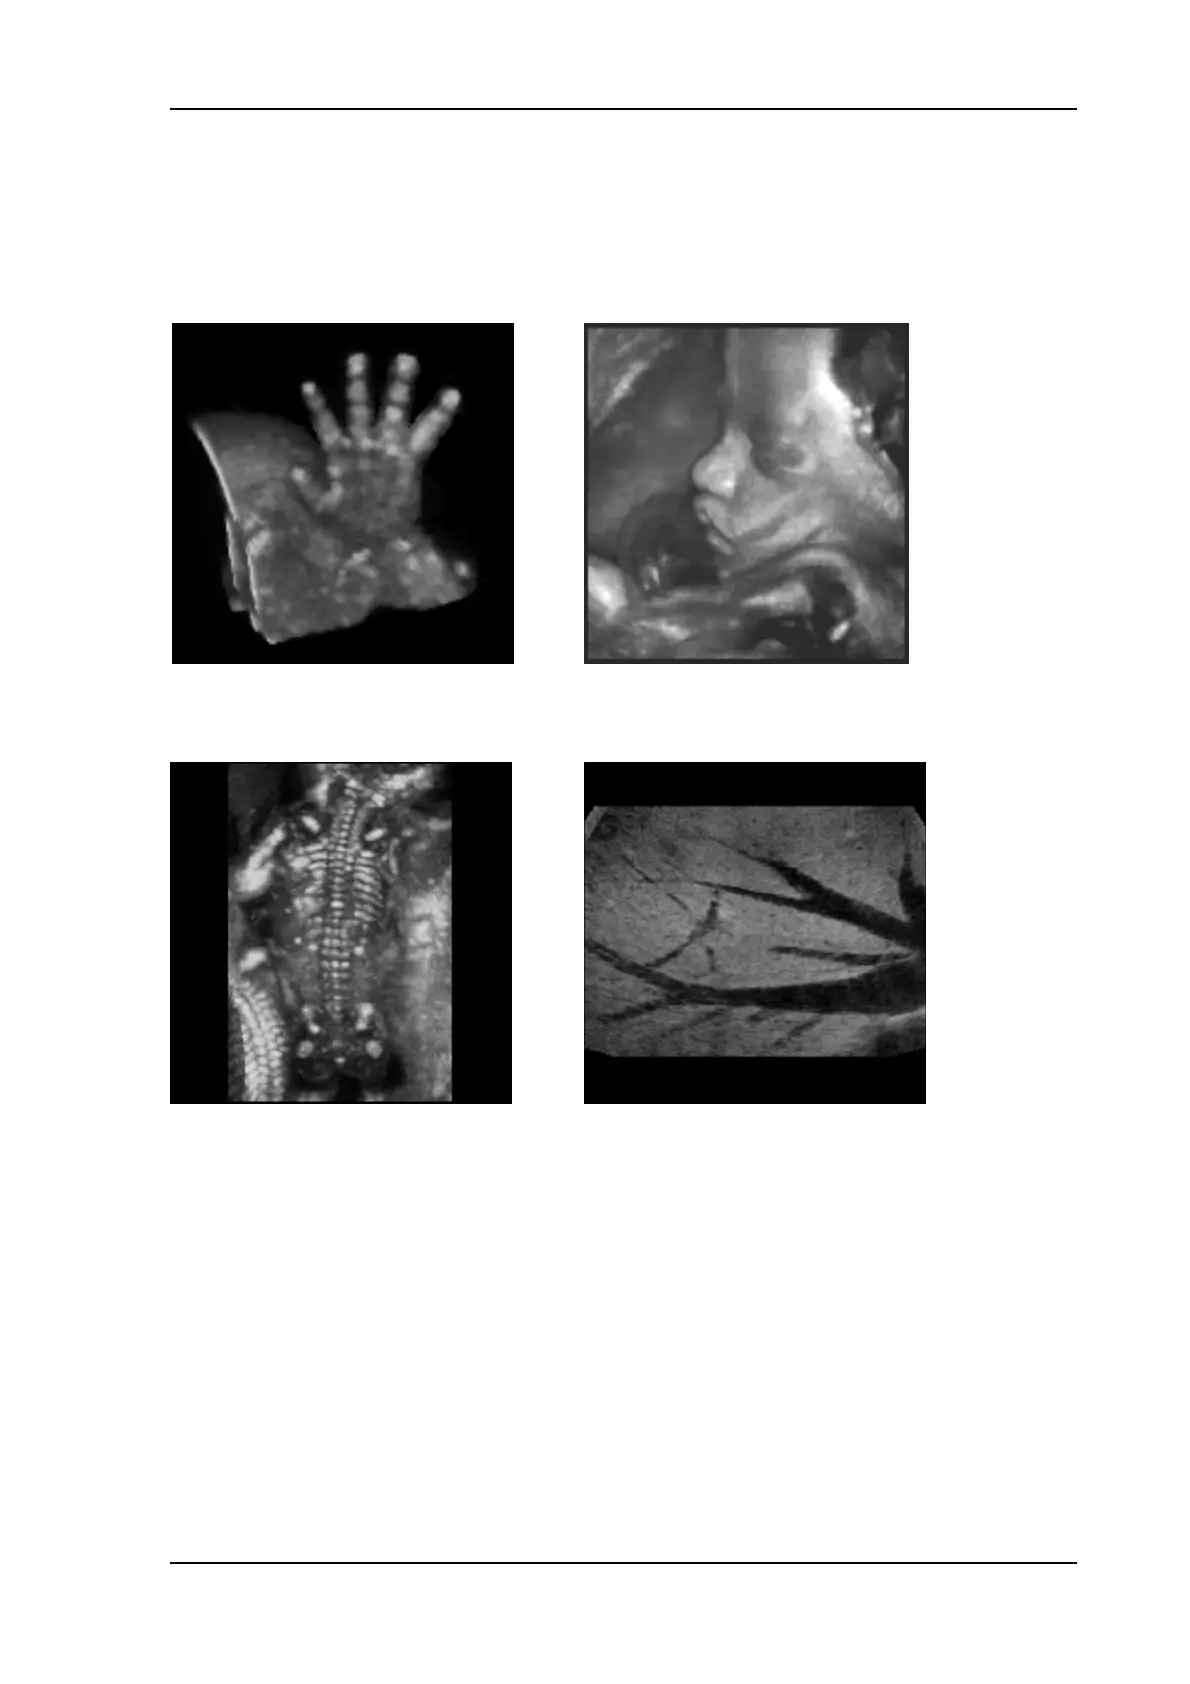

11.1.6.1 Examples of Rendered Images

Surface mode: gray rendering

Fetal hand Fetal face and umbilical cord

Transparent mode: gray rendering

Maximum mode: fetal skeleton Minimum mode: liver vessels